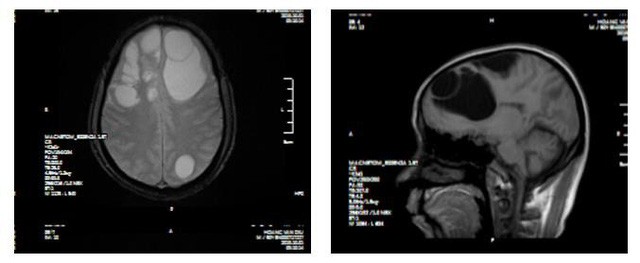

25/10/2019 22:30Hãi hùng hình ảnh sán 'làm tổ' trong não người đàn ông ở Lào Cai

Nam bệnh nhân là ông Hoàng Văn D (50 tuổi, Lào Cai), được chuyển tuyến từ Bệnh viện tỉnh Lào Cai xuống Bệnh viện đa khoa tỉnh Phú Thọ ngày 4/10 trong tình trạng giảm trí nhớ, giảm tri giác.

Khai thác tiền sử từ gia đình người bệnh cho thấy, khoảng một tháng nay ông D xuất hiện những biểu hiện giảm trí nhớ nhanh đến lạ kỳ, tứ chi có biểu hiện giảm vận động.

Tại Bệnh viện đa khoa tỉnh Phú Thọ, người bệnh được chỉ định chụp CT sọ não, kết quả cho thấy ổ sán não khổng lồ ở cả hai bán cầu trái và phù não diện rộng. Bệnh nhân được chỉ định can thiệp ngoại khoa.

Cuộc phẫu thuật kéo dài khoảng 2 giờ, ổ sán trong não đã được kíp phẫu thuật sử dụng các trang thiết bị hiện đại như kính hiển vi phẫu thuật, máy hút siêu âm cùng với kinh nghiệm chuyên môn đã lấy được trọn vẹn cả ổ nang sán.

BSCKII. Hà Xuân Tài - Phó trưởng khoa Ngoại thần kinh, Bệnh viện đa khoa tỉnh Phú Thọ chia sẻ: Kén sán não là bệnh nhiễm trùng hệ thần kinh do ấu trùng sán dây lợn sống ký sinh ở người gây ra. Bệnh gặp chủ yếu nơi có mức sống thấp, điều kiện vệ sinh môi trường kém, đặc biệt là ở những vùng có tập quán nuôi lợn thả rông hoặc ăn thịt lợn chưa được nấu chín. Bệnh kén sán não nếu không được phát hiện và xử trí sớm sẽ dẫn tới nhiều biến chứng cực kỳ nguy hiểm.

Các bác sĩ khuyến cáo, để phòng bệnh, người dân nên ăn chín, uống sôi, tuyệt đối không ăn tiết canh, gỏi sống,… Đặc biệt khi thấy xuất hiện các cơn đau đầu, co giật, người dân cần phải chú ý xét nghiệm các bệnh liên quan đến ký sinh trùng.